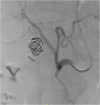

Presentation of case: A 76-year old female underwent laparoscopic cholecystectomy because of a severe acute on chronic cholecystitis. A massive arterial bleeding occurred during surgery, which was controlled with hemoclips. Approximately one week after surgery the patient developed severe colic pains and cholestatic liver enzyme alterations. Endo-ultrasound showed normal-width bile ducts, however during a subsequent ERCP haemobilia was observed. On computed tomography a pseudoaneurysm of the right hepatic artery was seen. Selective embolization was initially successful, however, a rebleed was observed two weeks later and a 6 × 50 mm Viabahn stent graft was placed in the right hepatic artery uneventfully. The patient remained free of complaints during 3-years of follow-up.